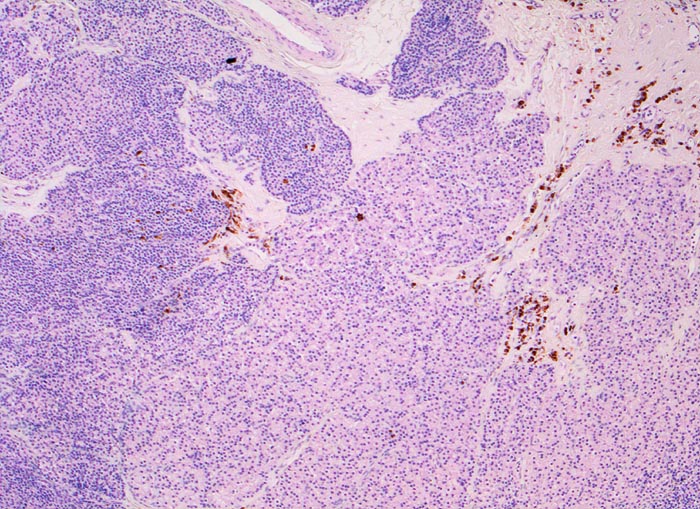

noduläre Nebenschilddrüsenhyperplasie

Nebenschilddrüse

Das Gewebe ist knotig strukturiert und enthält keine Fettzellen. In den Bindegewebssepten sind braun gefärbte Zellen nachweisbar, die siderinbeladenen Makrophagen entsprechen.

Der Patient leidet an einer chronischen Niereninsuffizienz. Die glomeruläre Filtrationsrate ist auf 25% reduziert. Unter anderem ist eine Hypokalzämie und eine Hyperphosphatämie vorhanden. Die Serumkonzentration des Parathormons ist erhöht. Die Diagnose eines sekundären Hyperparathyreoidismus wird gestellt.